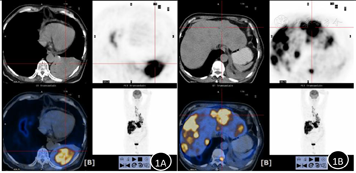

影像学检查:1.全身PET-CT示,左下肺软组织密度肿块,呈高代谢,考虑肺癌伴阻塞性炎症、肺不张;伴左胸腔少量积液;伴左肺门区、纵隔内、右胸廓入口区、肝门区、腹膜后腹主动脉旁多发淋巴结肿瘤转移;伴肝内肿瘤转移;伴胸11椎体肿瘤转移。PET-CT显示由于阻塞性肺炎伴肺不张暂不能清楚分辨左下肺占位边界,并可见伴肝内多发肿块(图1)。2.上腹部MRI示,肝脏弥漫性团块影,考虑多发转移瘤。左肝较大占位(红色箭头所指处)动脉期表现为周边环形强化征(图2)。